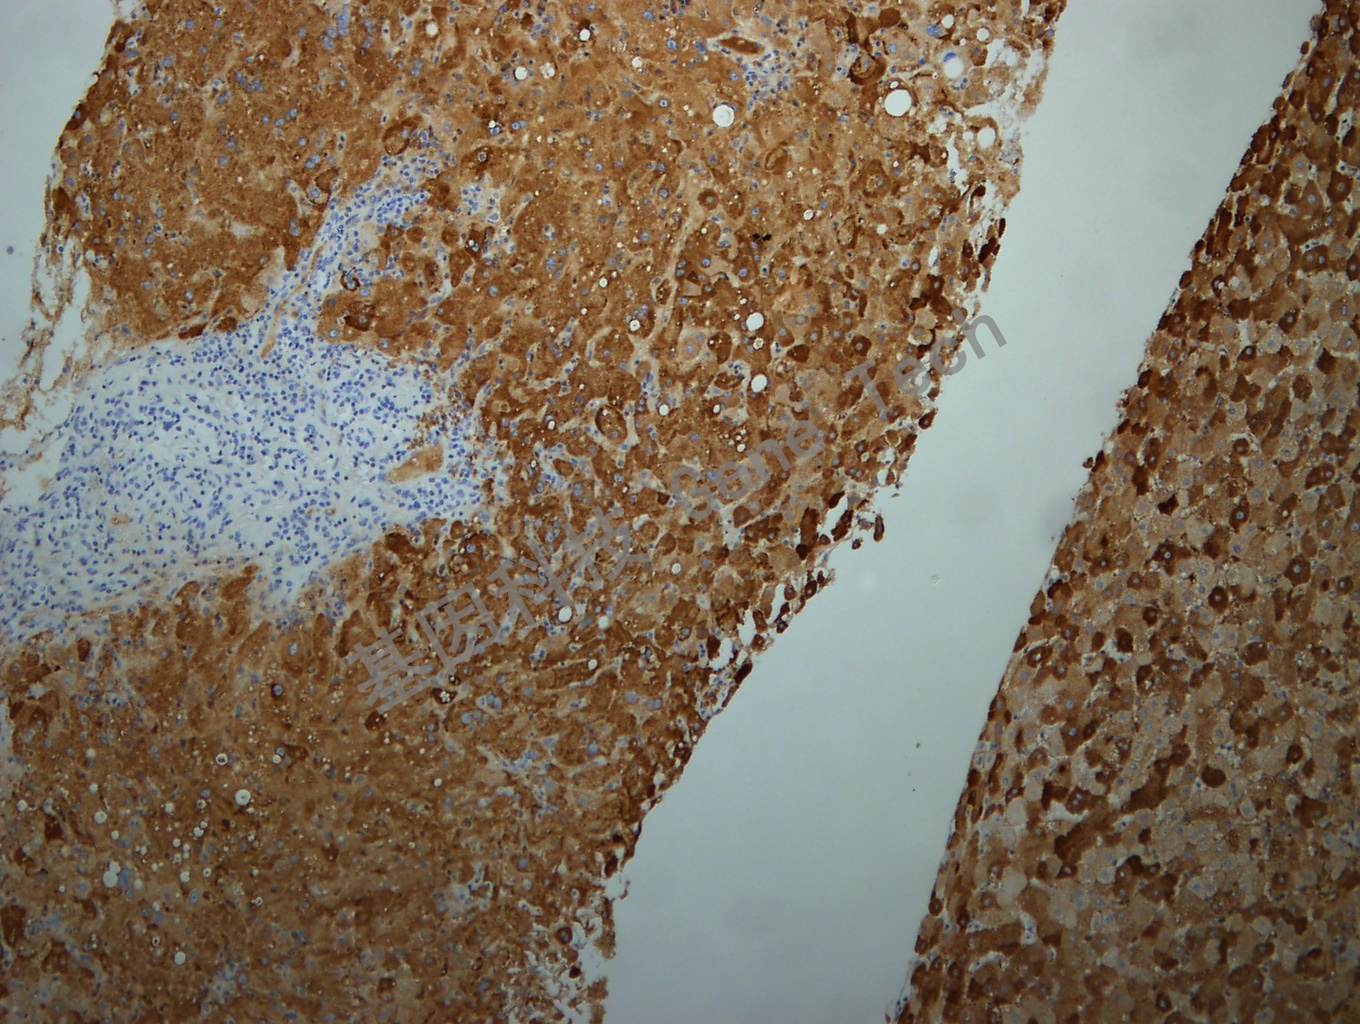

乙肝石蜡切片,用 HBsAg(GT2224)染色,细胞浆阳性,DAB 显色。